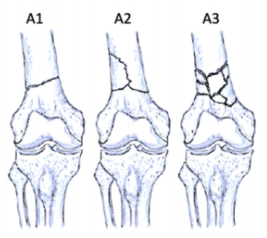

股骨遠端骨折分型

股骨遠端骨折可根據骨折模式、部位和膝關節受累情況進行分型 ,AO/OTA分型常用于對這些骨折進行分類。在每個類別中,骨折可根據復雜性和移位程度進一步分類,對于與全膝關節置換術(TKA)相關的假體周圍股骨遠端骨折,基于骨折移位和TKA股骨假體完整性的Lewis和Rorabeck分型(1997年)是最常用的分型:

A型:關節外骨折

不累及關節面

B型:部分關節內骨折

累及部分關節面但保持一定的關節匹配性

C型:完全關節內骨折

關節面完全破壞